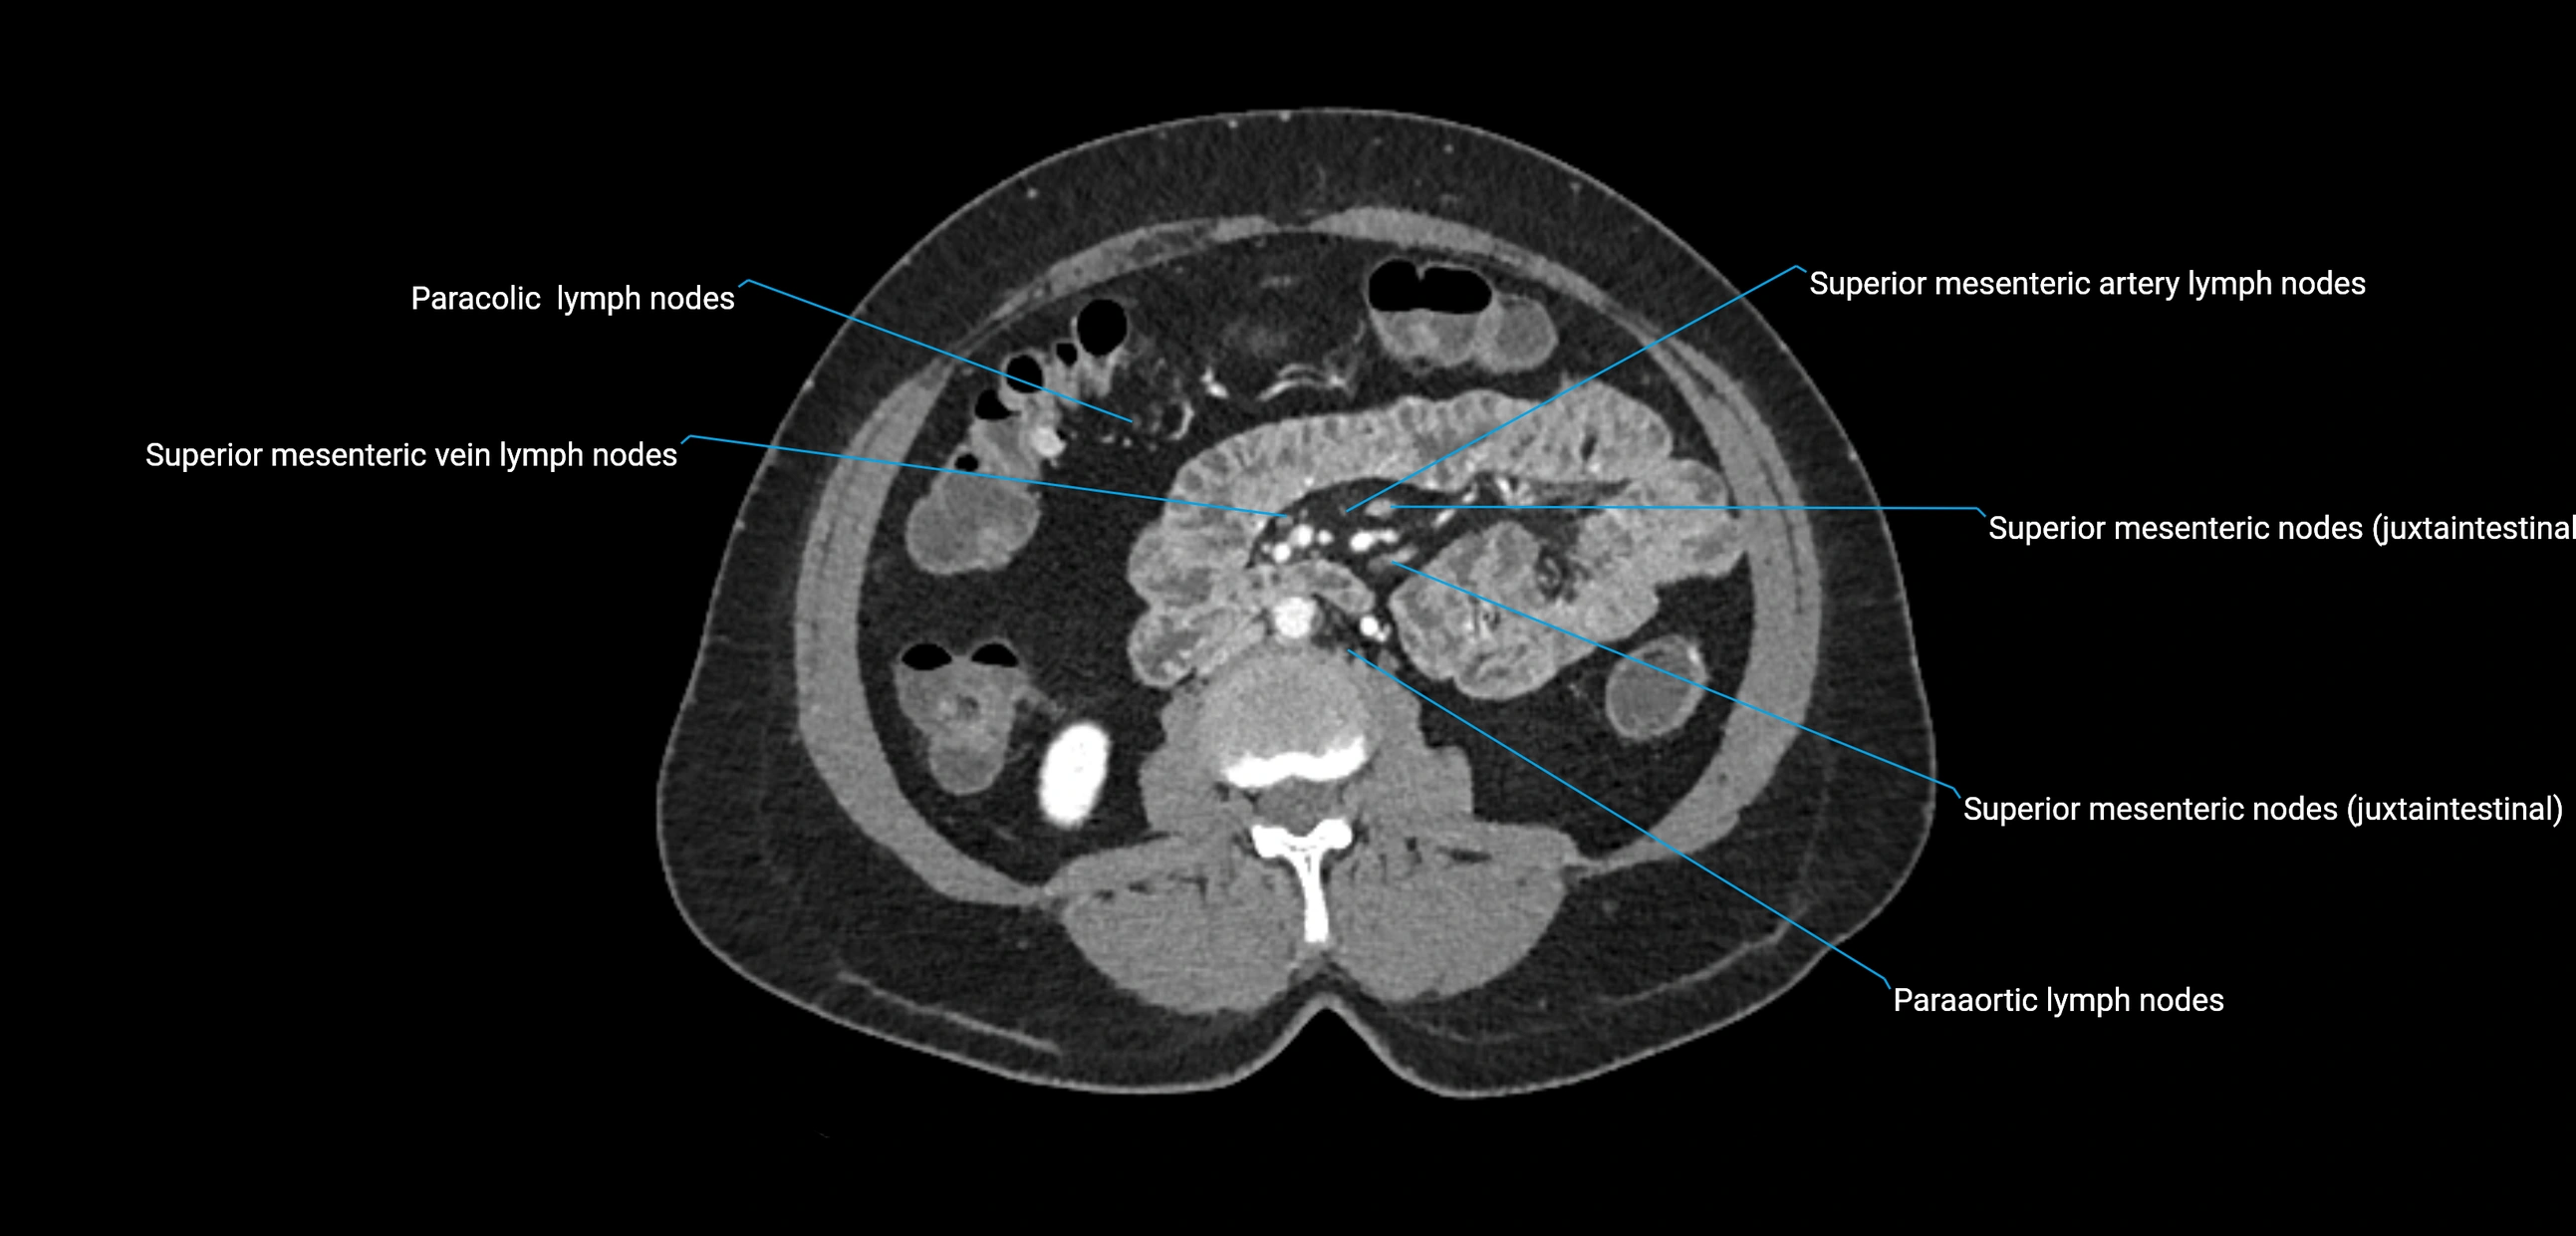

CT Appearance

CT Pre-Contrast:

• Nodes appear as soft-tissue density nodules adjacent to the aorta and IVC

• Calcification may be seen in chronic infections (e.g., tuberculosis)

CT Post-Contrast:

• Normal nodes enhance homogeneously

• Malignant nodes may show heterogeneous enhancement, central necrosis, or conglomerate formation

• Size >1 cm short axis is suspicious, though morphology and distribution are equally important